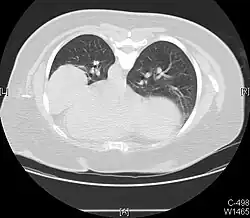

Asymmetric bullous emphysema

Bullous emphysema is a condition seen in patients with chronic obstructive pulmonary disease (COPD). The units making up the substructure of the lung (alveoli) become permanently enlarged due to the destruction of their walls. This leads to hyperinflation of the alveoli and, thus, the lungs. When this occurs asymmetrically, one lung can be larger than the other.[23] A severe variant of this condition is called giant bullous emphysema. On chest x-ray, one lung will be significantly more inflated than the other, causing a mediastinal shift. Bullous emphysema's radiographic appearance on x-ray mimics a tension pneumothorax. This presents a medical challenge as these diseases are treated differently despite appearing similarly on x-ray.[24][25]